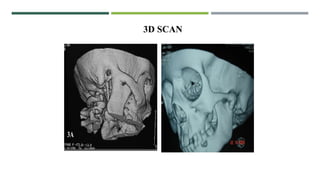

3D SCAN